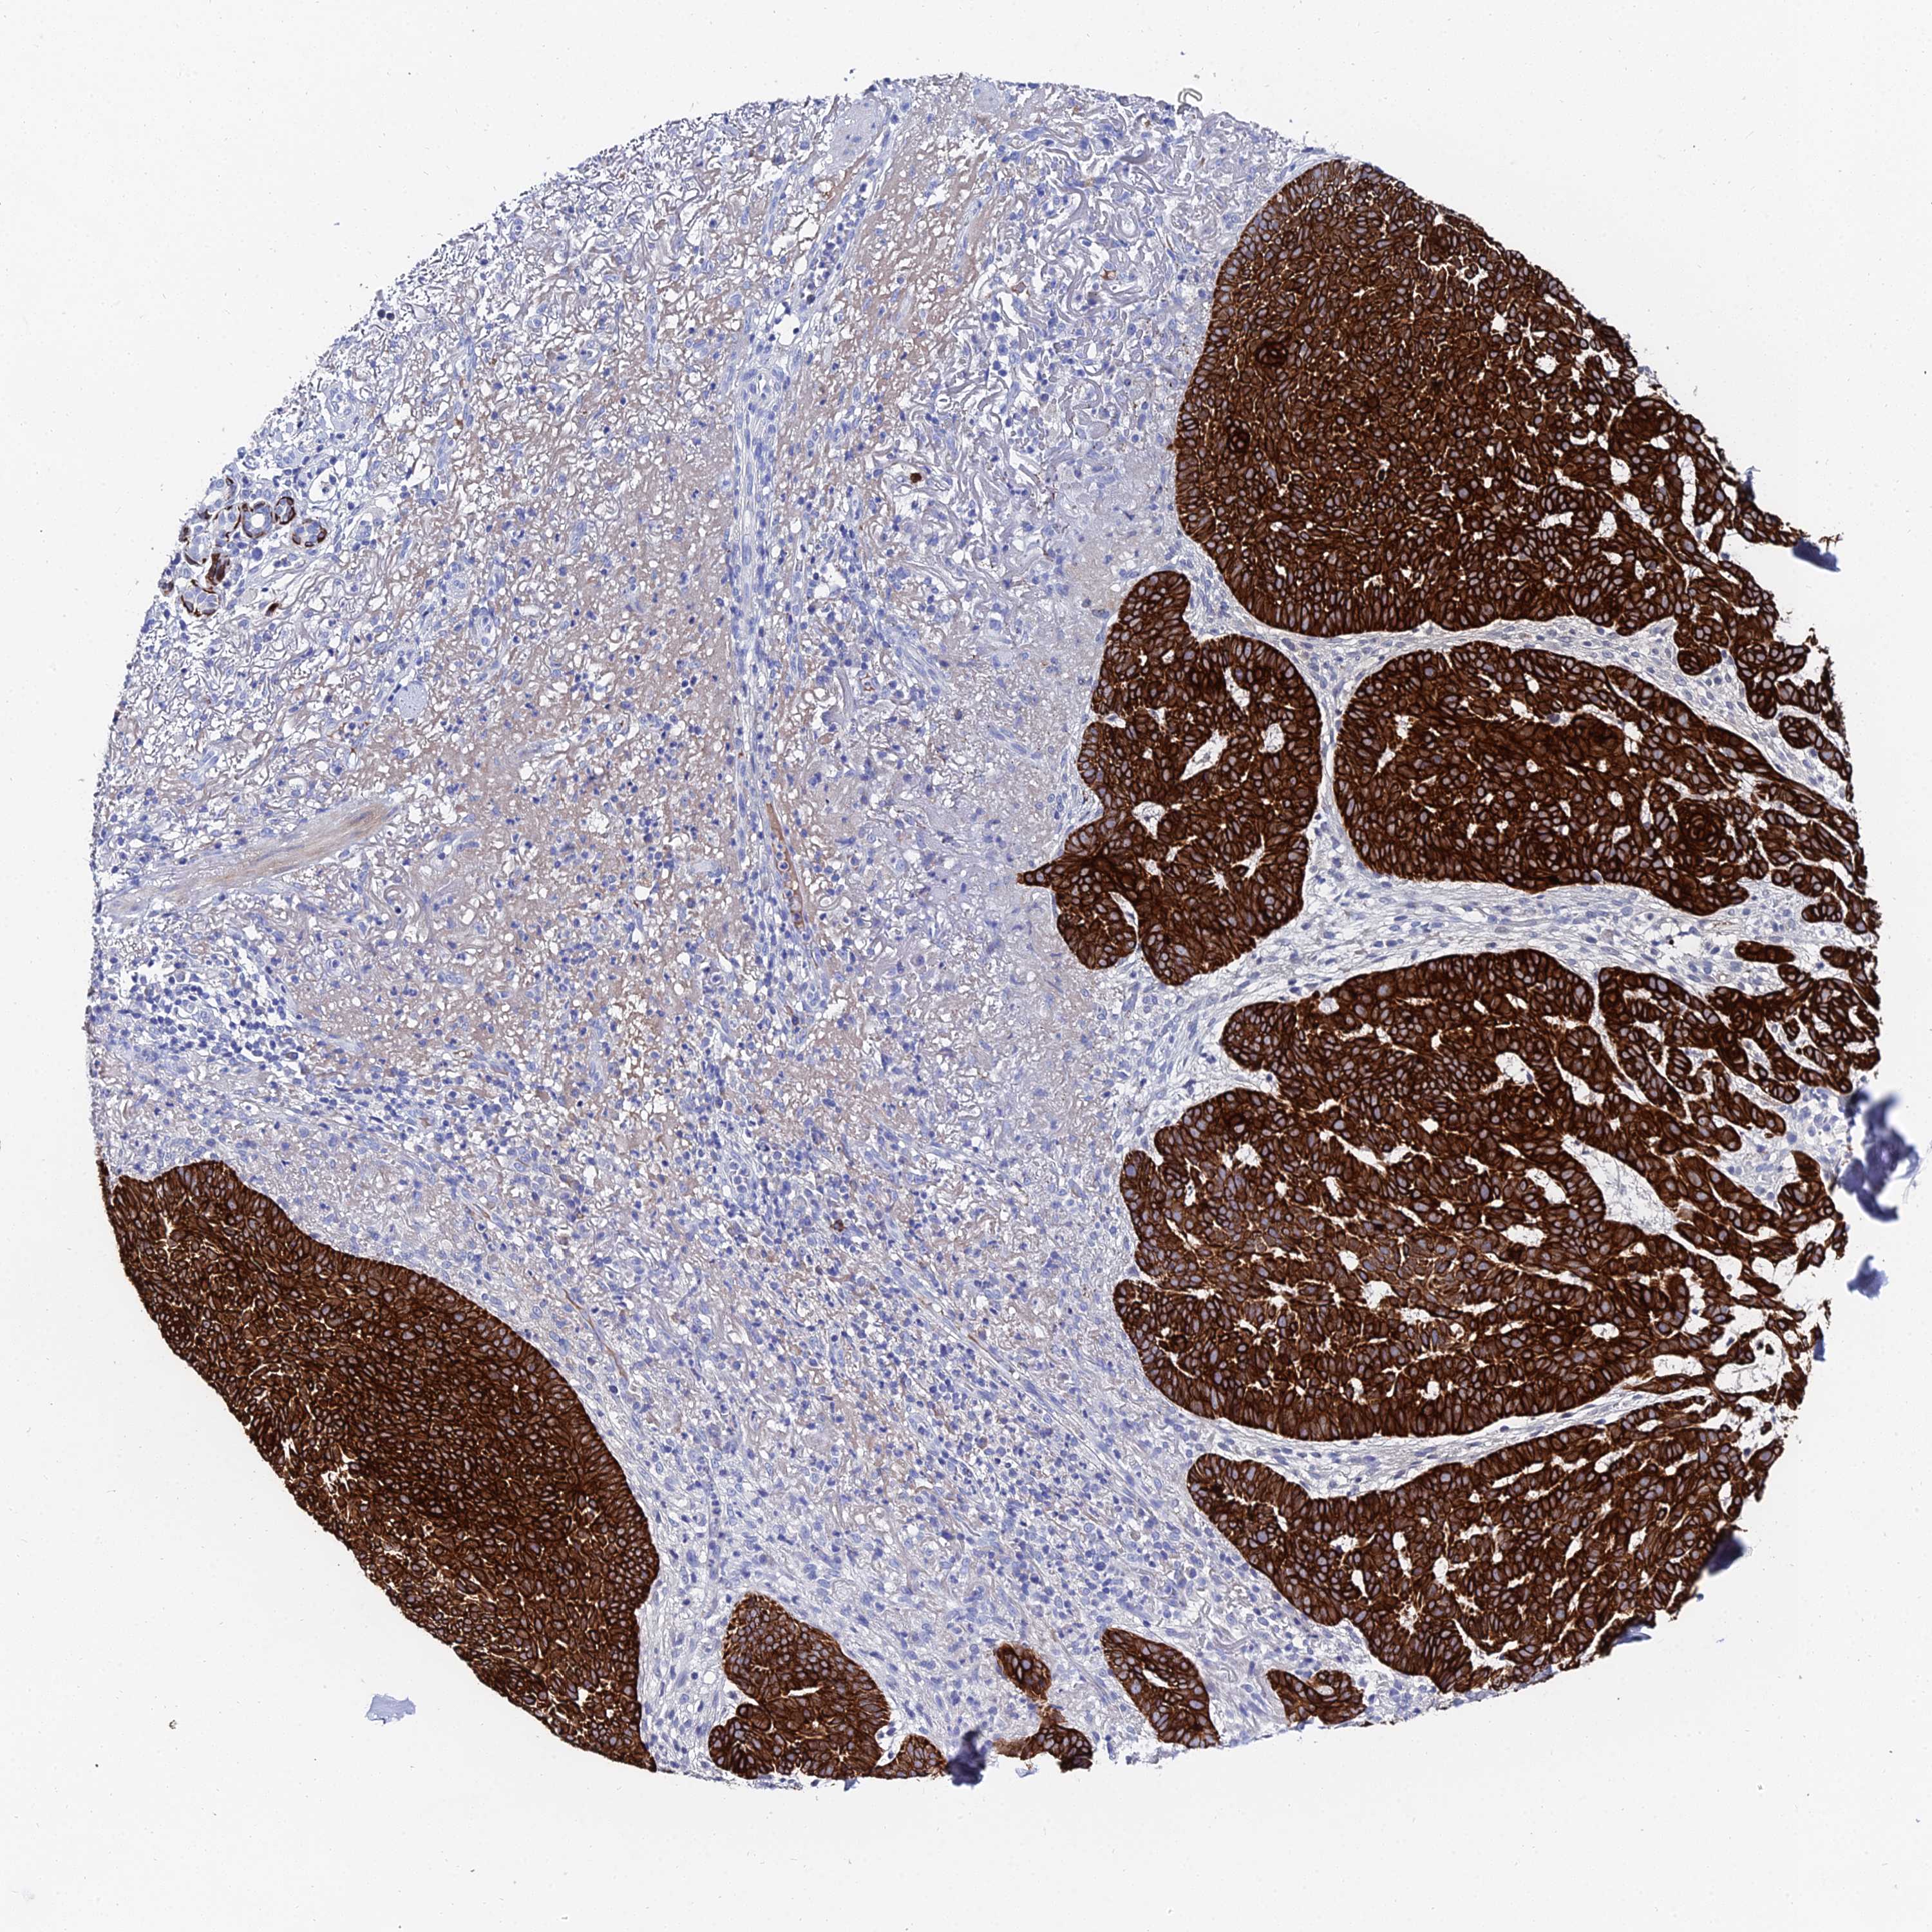

CANCER SKIN CANCER Show tissue menu

Basal cell and squamous cell cancer

SKIN CANCER - Protein expressioni

A mouse-over function shows sample information and annotation data. Click on an image to view it in a full screen mode. Samples can be filtered based on level of antibody staining by selecting one or several of the following categories: high, medium, low and not detected. The assay and annotation is described here.

Each image is clickable and will lead to virtual microscopy that enables deeper exploration of all samples and also displays staining intensity scores, fraction scores and subcellular localization as well as patient and tissue information for each sample.

Antibody HPA000452

Antibody CAB000029

Squamous cell carcinoma, NOS

Basal cell carcinoma

Squamous cell carcinoma, metastatic, NOS